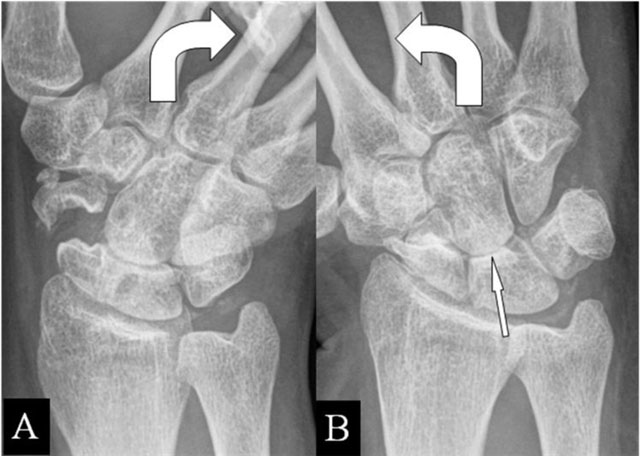

Figure 6

(Intra)scaphoid abutment. (A, B) PA plain mobility radiographs in ulnar and radial deviation. (A) Large diastasis in ulnar deviation between the scaphoid bone fragments. (B) Impaction of both fragments in radial deviation. Associated midcarpal osteoarthritis (arrow).